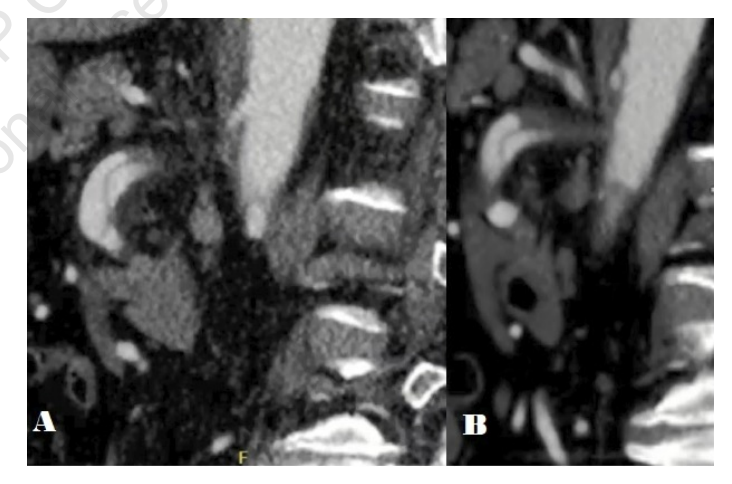

A 56-year-old male with a history of coronary artery disease who had undergone a prior cardiac catheterization with stent placement presented to our emergency department with a chief complaint of diffuse, progressively worsening, postprandial abdominal pain onset 6 hours earlier. A CTA was obtained, revealing an isolated superior mesenteric artery (SMA) dissection (Figure 1 and Figure 2). Vascular surgery was immediately consulted, and the patient was placed on a heparin infusion and transferred to our tertiary care facility. Upon examination, the patient had the typical out-of-proportion pain as seen with AMI, but he lacked any systemic signs of inflammation. Additionally, his vital signs and laboratory studies were all within normal limits. CTA findings revealed a dissected SMA with patent true and distally thrombosed false lumens without any evidence of bowel ischemia. Considering the patient’s presentation, physical examination, and imaging findings, admission was pursued for serial abdominal examinations, bowel rest, and anticoagulation with therapeutic heparin.